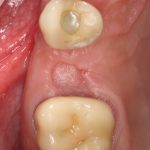

Вот клиническая картина через 4 месяца после ранее проведенной имплантации с остеопластикой:

Как видишь, коллеги из недалекой дружественной страны не осилили снятие швов. Мне это не нравится, хотя и объясняет, почему люди готовы ехать за тыщи километров ради 20-минутной операции удаления зуба мудрости.

Ну хорошо. Швы сняли. Делаем разрез. Обрати внимание, что после всех проведенных операций у нас остается очень небольшой по ширине слой жевательной слизистой оболочки: